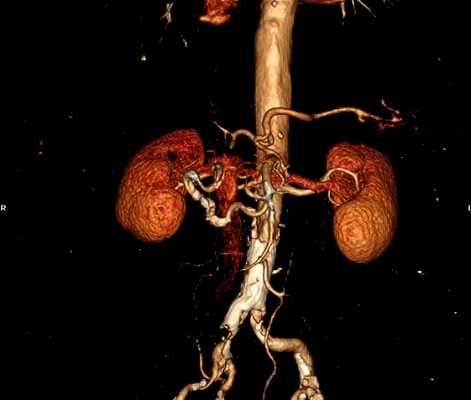

Мультиспиральная КТ ангиография, трехмерная визуализация

КТ ангиография позволяет создать трехмерную реконструкцию сосудистой системы на определенном участке. В отличие от классической рентгенографии в результате исследования получают серию послойных изображений с заданным шагом. Толщину сканирующего среза настраивают индивидуально (от 1 мм). На основании поперечных, боковых и прямых фото создают 3D-модель рассматриваемой области.

Контрастная КТ ангиография почечных артерий

При наличии аневризмы раствор заполняет патологический карман, показывает расположение и размеры очага.